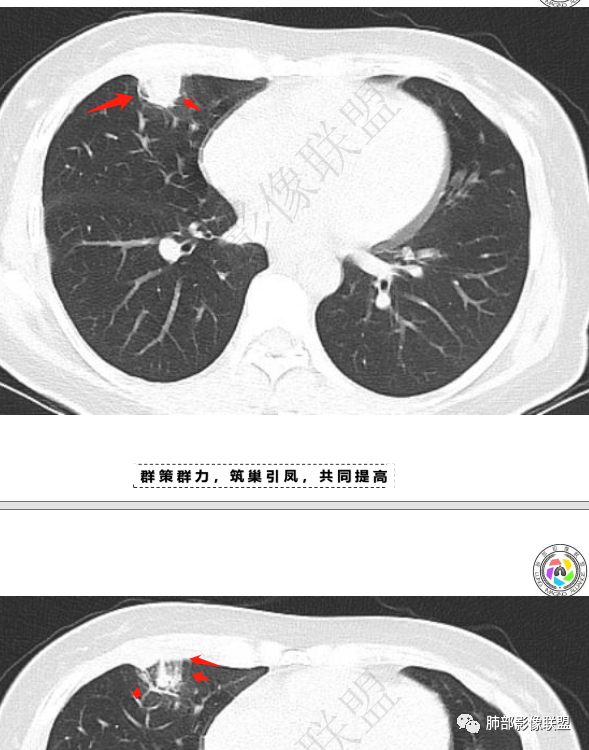

青年女性,胸痛1年,慢性病程

肺内多发小斑片状高密度影,密度不均匀,边缘稍平直

胸膜多个结节,附近胸壁脂肪间隙密度增高,提示有胸壁蔓延或侵犯。

胸膜区病灶周围肺内有小斑片状影,内有条索影,而非放射状,提示提示病灶累及肺内。周围渗出明显——良性肿瘤排除

一月后复查,肺内病灶密度增高,边缘收缩,体积缩小,提示渗出朝增生转变;胸膜病灶缩小。